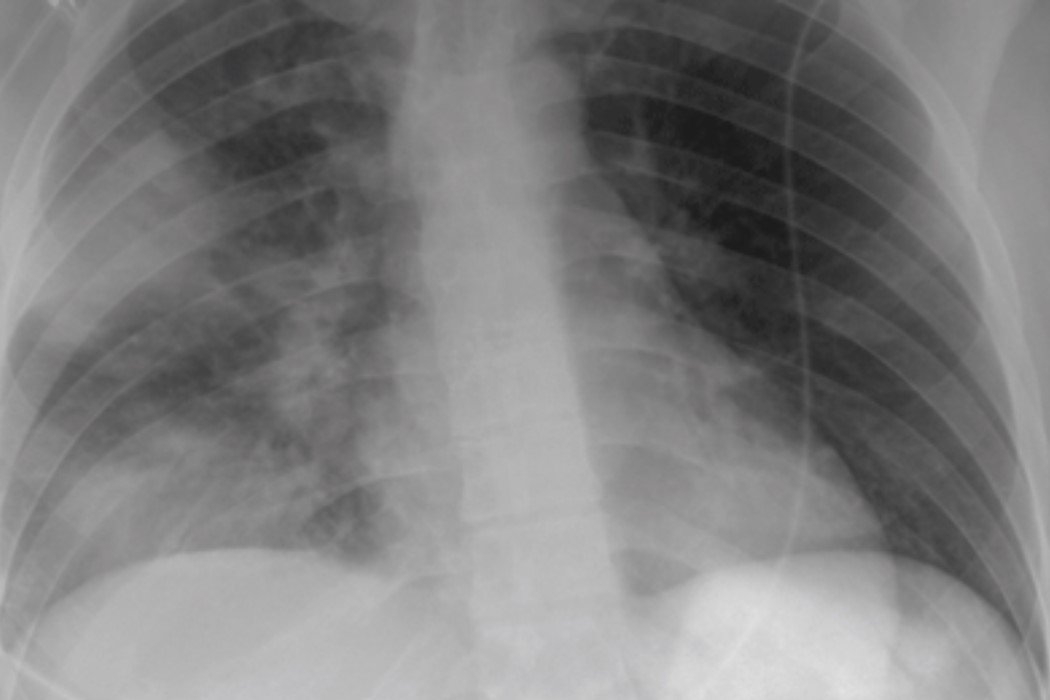

The AFROCAP-PILOT study, led by the Ifakara Health Institute, marks a significant step in advancing research on community-acquired pneumonia (CAP) among adults in sub-Saharan Africa. It seeks to generate critical evidence to improve the diagnosis, treatment, and overall management of pneumonia across the region.

Community-acquired pneumonia remains a leading cause of illness and death globally. However, while high-income countries have robust data systems, sub-Saharan Africa still faces a shortage of comprehensive, standardized data on adult pneumonia cases.

Mortality rates in the region are significantly higher, yet most available studies are limited to small, single-center investigations. AFROCAP seeks to change this by laying the groundwork for a large-scale, multi-country research network focused on pneumonia.

- Analyze the clinical course and causes of pneumonia in adults

- Examine links between pneumonia and conditions such as HIV and tuberculosis

The research will be conducted at St. Francis Regional Referral Hospital in Tanzania and will enroll approximately 300 adult participants, including, 200 patients with confirmed pneumonia and 100 patients with tuberculosis presenting similar symptoms